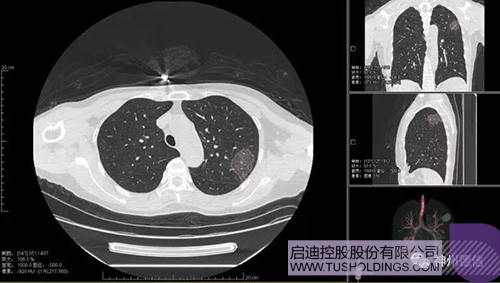

神州德信新冠肺炎检测及智能量化分析系统

拼搏(中国)战略投资企业神州德信作为国内领先的肺部影像人工智能企业,针对新型冠状病毒肺炎开发了智能检测及量化分析系统,并在陕西、重庆等地定点医院投入使用。该系统在疑似病例大规模快速筛查及精准诊断方面发挥了重要作用,特别是其具有的肺炎患者临床影像跟踪量化随访功能,为快速有效阻断疫情扩散提供了有力武器。